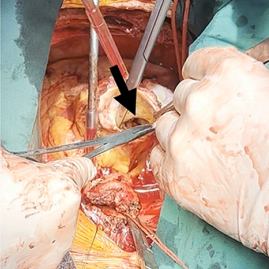

经胸超声心动图提示:人工主动脉瓣可见赘生物(29×9mm,活动度大,且随心动周期显著摆动)(图1);重度瓣周漏;瓣叶撕裂并伴有广泛瓣周脓肿形成。主动脉根部扩张,无冠窦明显膨出,并可见右冠窦至右心房瘘管形成。其余可见严重二尖瓣反流、中度三尖瓣反流及三尖瓣上赘生物附着。

图1

人工主动脉瓣膜上广泛赘生物附着

窦扩张伴瓣周脓肿